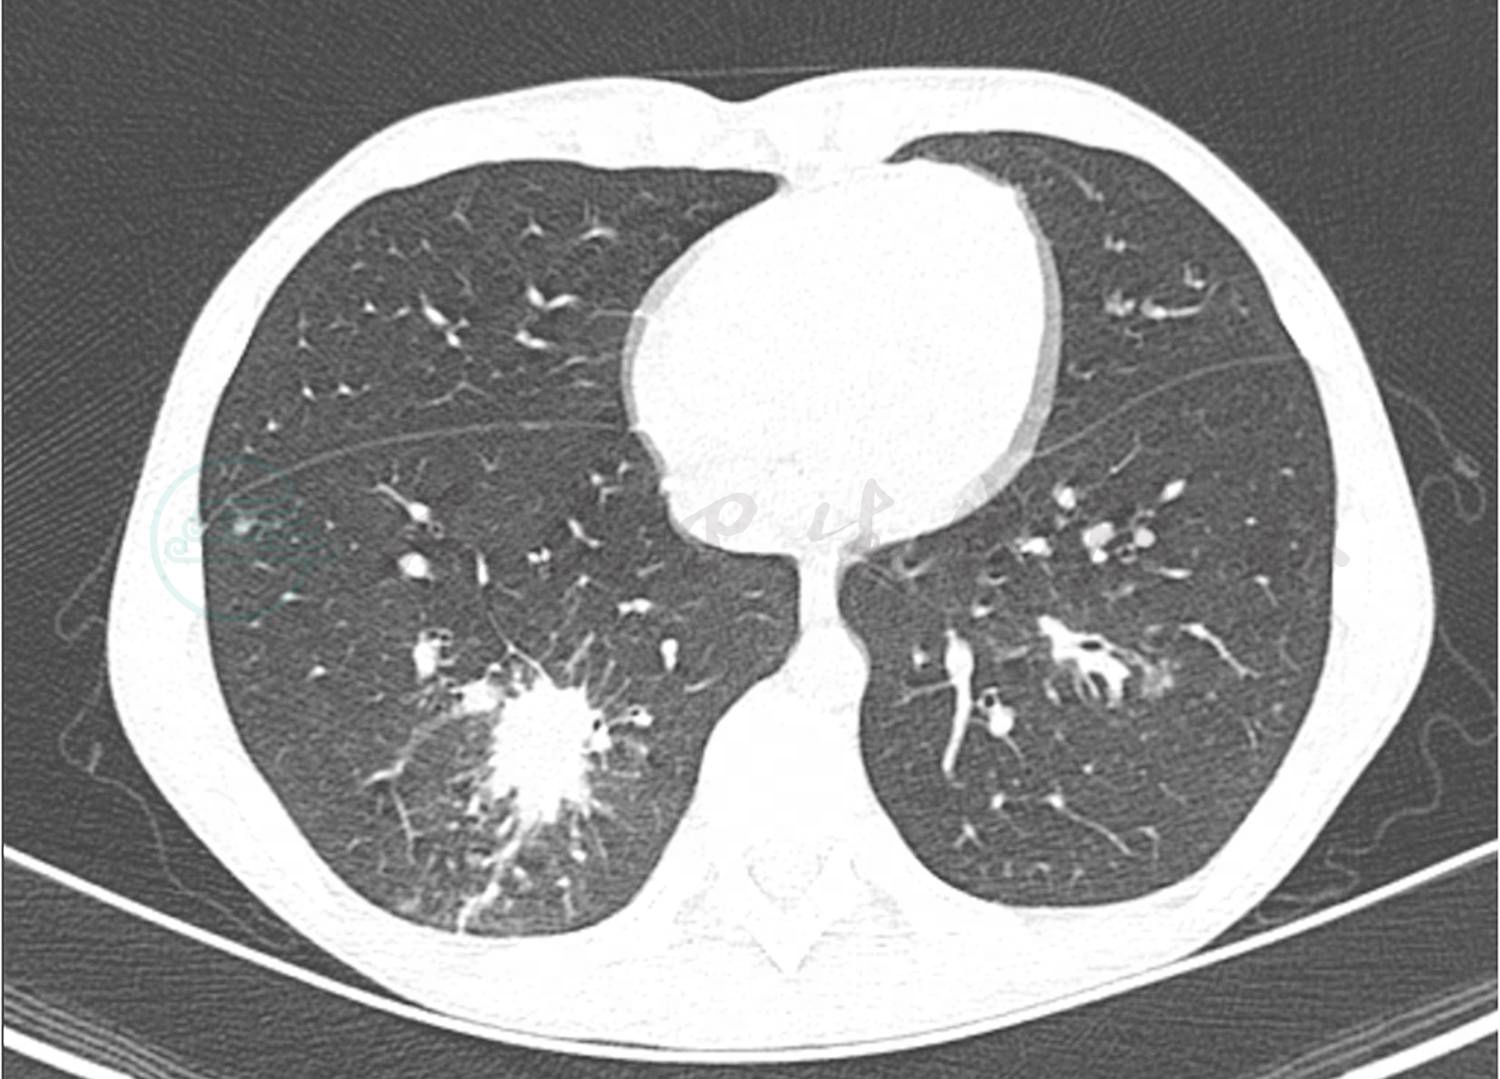

转入笔者科室立即完善相关病原学检查提示GM试验阴性,1,3-β-D葡聚糖 <10µg/L,痰培养及血培养均阴性,PPD 阴性,结核斑点试验(T-spot)阴性,以上检查均未找到明确病原体。入院第5天完善纤维支气管镜检查,镜下示(图3)右肺下叶B10亚段可见大量黄白色类干酪样物质阻塞及坏死黏膜附着管壁,予毛刷刷检,刷检时黏膜有出血,予万分之一盐酸肾上腺素冲洗止血,将刷检物质送病理检查。根据镜下改变,高度怀疑支气管内膜结核及真菌感染。经胸科医院会诊,建议诊断性抗结核治疗,但家属拒绝。给予患儿伏立康唑抗真菌治疗,7天后体温恢复平稳,无咯血,复查肺CT(图4)提示右肺下叶后底段支气管旁高密度团块影较前减小。入院第12天病理结果回报(图5)提示炎性渗出坏死物及霉菌。

图3 入院第5天支气管镜下改变